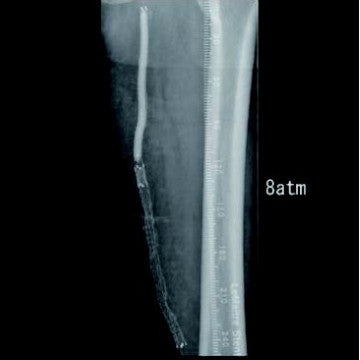

[背景] 左間欠性跛行で14年前に左SFAにベアナイチノールステント6 mm × 120 mm 2本が留置されている(図1)。約7年前に左間欠性跛行が増悪し、来院。外来での超音波検査でベアステントの完全閉塞を認めた(図2)。高度の跛行があり、再治療を実施した。

[治療] 右総大腿動脈(common femoral artery:CFA)を逆行性にエコーガイド下に穿刺。山越えで左 CFAまで6 Frガイディングシースを進めた。造影で左SFA起始部付近からベアステント遠位端のやや中枢側まで、TOSAKA分類3のISO病変があることを確認した。ところどころ病変が硬く、0.014 inchガイドワイヤーの先端2.8 gと先端12 gを順次使用して閉塞部位を突破した。PTAバルーン4 mm × 250 mmで前拡張したのち、病変部をカバーするように左SFA末梢側から左SFA起始部にかけてバイアバーン® ステントグラフト6 mm × 250 mmと6 mm × 100 mmを留置し、閉塞したベアステントをフルカバーした。バルーン5 mm × 220 mmで後拡張を実施、血管内超音波(IVUS)と造影で病変部の良好な拡張、血流を確認し手技を終了した(図3)。足関節上腕血圧比(ABI)は0.68から0.92に改善した。さらに6年が経過し、間欠性跛行の再燃があり、ステントグラフトは開存していたが(図4-1)、さらに末梢の膝窩動脈での石灰化プラークによる閉塞病変(図4-2)が原因と考えられた。アテレクトミーデバイスとDCBで膝窩動脈病変を治療して症状は消失した。run offが不良であったにもかかわらず、中枢側のステントグラフトが6年間開存していたことは特筆すべきことである。同患者については現在まで15年にわたり経過をみているが、経年的に動脈硬化が進んでおり、通常のステントやバルーンでの治療部は再治療を繰り返している。その中でステントグラフトを留置した長区間ISO病変は6年間開存を保っていたというのは、物理的に内膜過形成をシャットアウトするステントグラフトでしかみられない現象であると思われる。ISO病変に対するバイアバーン® ステントグラフトの使用が保険適用されるようになったことは、血管内治療医や患者に福音をもたらしたのではないだろうか。